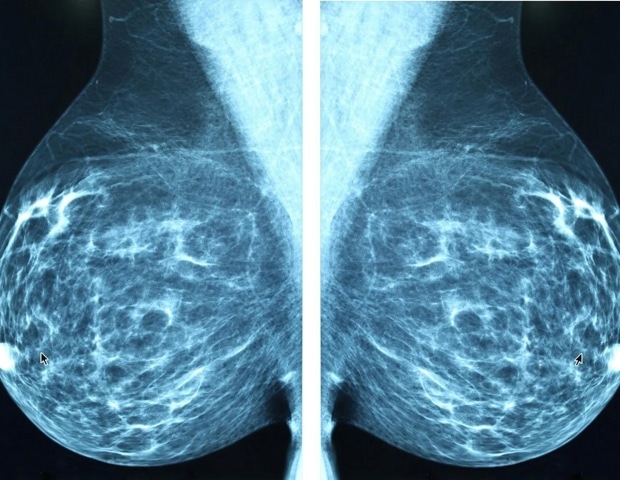

L’acupuncture réelle et simulée étaient plus efficaces pour améliorer la déficience cognitive perçue par les survivantes du cancer du sein par rapport aux soins habituels, tandis que l’acupuncture réelle était supérieure à l’acupuncture simulée pour améliorer la fonction cognitive objective, selon les résultats de l’essai clinique randomisé de phase II ENHANCE présenté au San Antonio Breast Cancer Symposium (SABCS), tenu du 9 au 12 décembre 2025.

Plus de 40 % des survivantes du cancer du sein éprouvent des difficultés cognitives liées au cancer, parfois appelées « brouillard cérébral » ou « chimio-cerveau », selon Jun J. Mao, MD, MSCE, titulaire de la chaire Laurance S. Rockefeller en médecine intégrative et chef du service de médecine intégrative et de bien-être au Memorial Sloan Kettering Cancer Center. « Les difficultés cognitives liées au cancer peuvent rendre l’exécution des tâches quotidiennes plus difficile et réduire la qualité de vie globale », a expliqué Mao. « Malheureusement, il existe très peu de traitements étayés par des preuves de ce problème. »

L’essai clinique a porté sur 260 femmes ayant des antécédents de cancer du sein de stade 0 à 3, qui ont terminé leur traitement, ne présentaient aucun signe de cancer et présentaient des difficultés cognitives et une insomnie modérées ou plus importantes liées au cancer. Les participants ont été répartis au hasard pour recevoir une véritable acupuncture (129), une acupuncture simulée (70) ou des soins habituels (61). Des traitements d’acupuncture réels ou fictifs ont été administrés une fois par semaine pendant 10 semaines, et la fonction cognitive a été évaluée au départ, à 10 semaines et à 26 semaines.

La fonction cognitive perçue a été mesurée à l’aide de l’évaluation fonctionnelle de la thérapie anticancéreuse – Fonction cognitive (FACT-Cog PCI), un résultat validé rapporté par les patients qui demande aux patients de répondre à une enquête sur la façon dont ils ressentent que leur mémoire, leur attention et leur capacité à effectuer des tâches quotidiennes ont été affectées. La fonction cognitive objective a été mesurée via le Hopkins Verbal Learning Test-Revised (HVLT), qui mesure les performances de mémoire, d’apprentissage ou d’attention à l’aide de tâches standardisées.

« Ces deux mesures capturent différents aspects de la cognition et ne s’alignent souvent pas », a déclaré Mao. « Dans notre étude, parmi les participants ayant signalé des difficultés cognitives modérées à sévères et remplissant les conditions d’éligibilité à l’inscription, seuls 30 % répondaient aux critères de déficience cognitive objective tels que mesurés par le HVLT. Cette inadéquation met en évidence l’importance d’utiliser les deux outils ensemble car ils fournissent une image plus complète. «

Après 10 semaines, les patients des groupes d’acupuncture réelle et d’acupuncture fictive ont montré une amélioration cliniquement significative de la déficience cognitive perçue, mesurée par les scores FACT-Cog PCI : une amélioration de 10,3 points et une amélioration de 10,5 points, respectivement, par rapport à une amélioration de 4,8 points dans le groupe de soins habituels. L’acupuncture réelle a également montré une double amélioration dans la réduction des troubles cognitifs perçus par rapport aux soins habituels à 10 semaines et à 26 semaines, tandis que la différence entre l’acupuncture réelle et fictive n’était significative à aucun des deux points.

Alors que l’acupuncture réelle améliorait les scores HVLT, l’acupuncture simulée n’avait aucune différence sur la fonction cognitive objective. À la semaine 10, l’acupuncture réelle était significativement meilleure que l’acupuncture simulée avec une différence de 4 points dans les scores HVLT. Dans l’ensemble, l’acupuncture réelle et les soins habituels ont montré des résultats similaires en termes d’amélioration de la fonction cognitive objective. Cependant, dans le sous-ensemble de patients présentant une fonction cognitive objective altérée au départ, l’acupuncture réelle était associée à une tendance prometteuse en matière d’amélioration de la mémoire par rapport aux soins habituels et à l’acupuncture simulée.